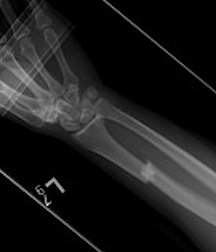

Xray

DRUJ disruption

- widened space between radius and ulna on AP

- dorsal subluxation / dislocation of ulna on lateral

- radial shortening > 5 mm

- ulna styloid fracture

Shortening of radius with disruption of DRUJ on lateral

Widening of interval between radius and ulna / clear disruption of DRUJ

Concern for disruption of DRUJ on lateral